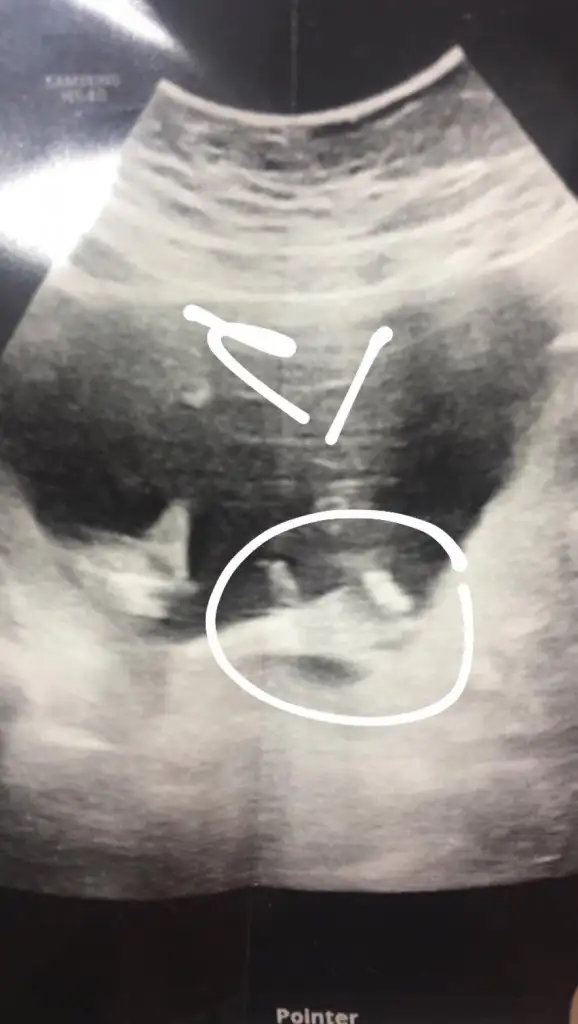

sabah akşam bekliyorum bugün umut yok da. ben haber veremezsem de elçin verir size. dua edin

evdeyim. ablam da nişandan sonra 1 hafta kadar beklemiş. o kadar olmasa da birkaç gün sancıyı beklicem sanırım. şuan sancı yok evde bekleyip dakika tutucam. hastane yakın 15 dk. doktorumla da irtibattayımevde mi hastanede misin? hadi inşallahh sağlıkla kucağına al kuzum